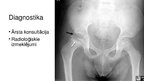

Pertesa slimība